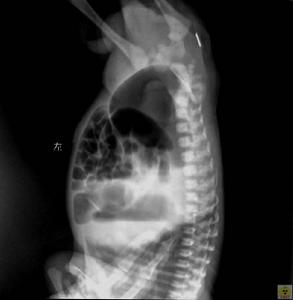

先天性肛門閉鎖對本病的診斷,主要根據患兒哭時隨著腹壓的增高或降低,會陰部也隨著凸起或凹陷。用一手輕壓迫下腹部,一手觸摸會陰部,則有波動感。若將患兒臀部抬高,肛門部扣診呈鼓音。X線可幫助進一步確診。

先天性肛門閉鎖新生兒出生後無胎糞排出,餵奶後腹部膨脹,出現嘔吐,繼爾皮膚乾癟、消瘦,若出現這種症狀,即應考慮鎖肛症,若發現和治療不及時,則易導致腸梗阻,腸壞死,致新生兒死亡。